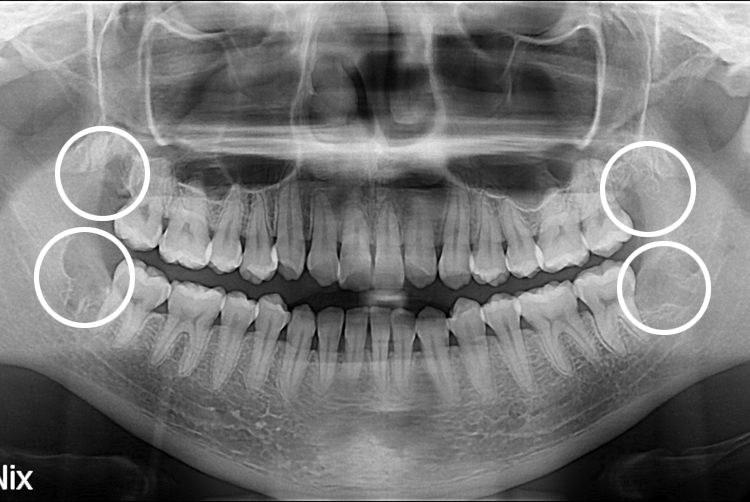

[사랑니] 단순매복 + 복잡매복 + 완전매복 사랑니 발치

치료전 : 2017-10-20